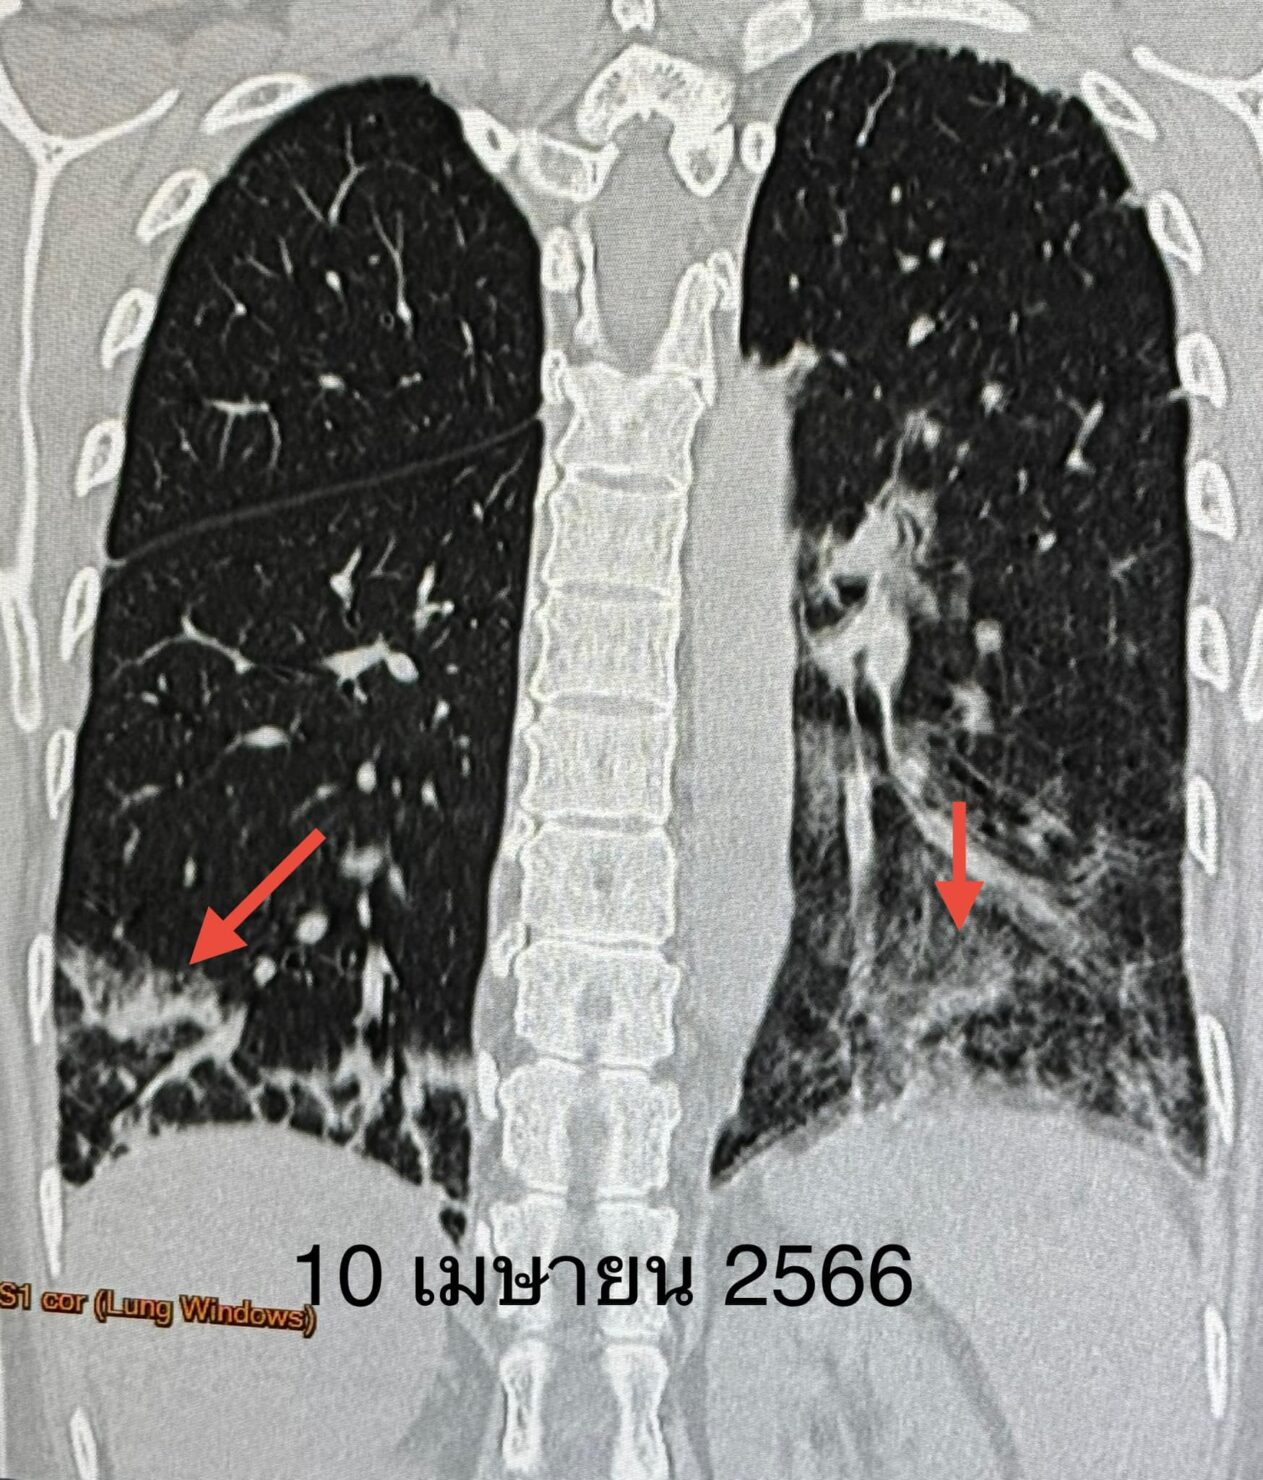

ผู้ป่วยได้วัคซีนไฟเซอร์เข็มที่ 3 เดือน ม.ค. 2566 เพราะกลัวว่าหากติดไวรัสโควิด-19 อาจป่วยรุนแรง เนื่องจากกำลังกินยากดภูมิคุ้มกัน ปรากฏว่า 5 วันหลังฉีดวัคซีนไฟเซอร์ ผื่นที่หน้า ข้อมือ ข้อศอก คอ หลังส่วนบน กลับมาเป็นมากขึ้น ไอ เหนื่อยเวลาออกกำลังกาย เอกซเรย์ปอดและคอมพิวเตอร์ปอดเห็นฝ้าขาวเพิ่มขึ้นที่ปอดด้านล่างทั้ง 2 ข้าง(ดูรูป)

ผู้ป่วยติดเชื้อไวรัสโควิดครั้งแรกวันที่ 5 ธค. 2566 มีอาการน้อยมาก ได้ยาโมลนูพิราเวียร์ หายเร็วทั้งๆที่กินยากดภูมิคุ้มกัน ไม่มีอาการหลังการติดเชื้อไวรัสโควิด ค่อยๆ ปรับลดยากดภูมิคุ้มกันลงเรื่อยๆ ผิวหนังกลับมาเป็นปกติ เอกซเรย์ปอด และคอมพิวเตอร์ปอดดีขึ้นเกือบปกติ(ดูรูป) ทำสมรรถภาพปอดความจุของปอดกลับมาปกติ วันที่ 17 ธ.ค. 2567 หลังจากรักษา 2 ปีกว่า ได้หยุดยากดภูมิคุ้มกันทุกตัวเหลือแต่ไฮดรอกซีคลอโรควิน กิน 1 เม็ดวันเว้นวัน ค่าอักเสบของเลือดปกติ ESR 8, hs-CRP 0.4